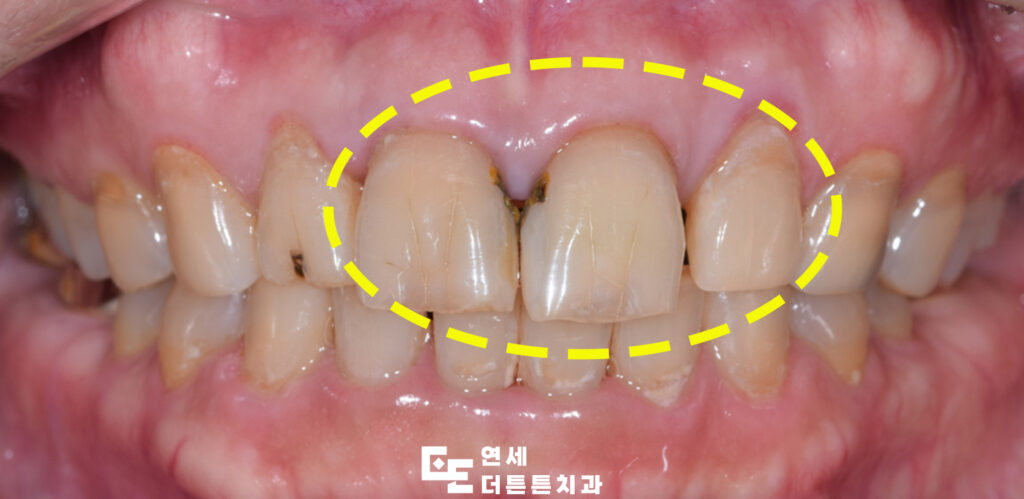

오늘은 외상으로 인해 앞니 크라운을 진행하신 환자분을 소개해 드리려고 합니다.

환자분께서는 앞니의 외상으로 인해 치료를 받으시려고 방학역치과에 내원해 주셨는데요. 자연치를 보존하고 외상으로 인한 충격을 보호하기 위해 크라운 치료를 계획하였고 진행하시기로 하였습니다. 임플란트보다 부담이 덜한 보철치료 가운데는 크라운을 들 수 있는데 크라운은 치아의 머리 부분 일부를 삭제해 모자처럼 인공재료를 덮어씌우는 형태의 치료로 임플란트가 치아 발치 후 식립하는 형식이라면 크라운 치료는 발치를 하지 않고 기능을 회복할 수 있도록 한다는 점이 특징입니다. 보통 치아머리 부분이 외상으로 인해 파절 되거나 썩어 없어진 경우 주로 활용되어 치아 머리가 부러져서 뿌리만 남은 경우라도 잇몸과 뿌리 상태가 양호하다면 기둥(포스트)을 세워서 머리를 새로 만들어서 치료가 가능하며 이런 경우 기둥으로 치아 머리를 만든 후 치아를 다듬어서 크라운 제작을 하게 됩니다.